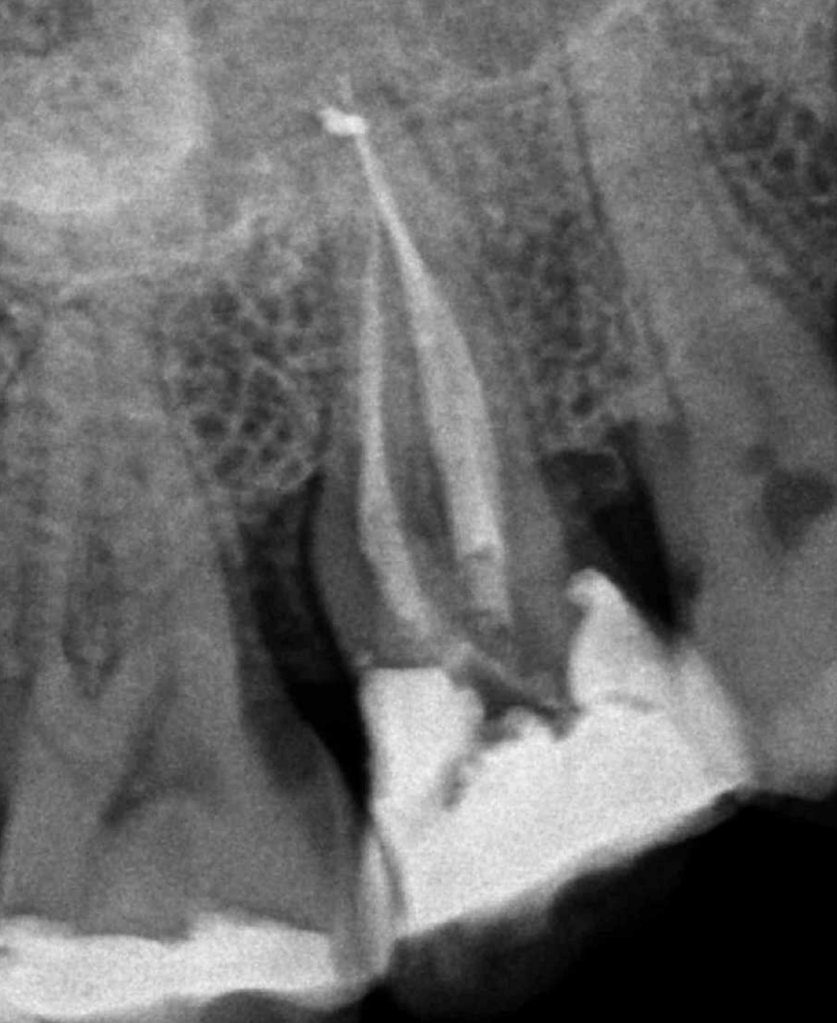

CALCIFICADOS

Premolar calcificado lesion